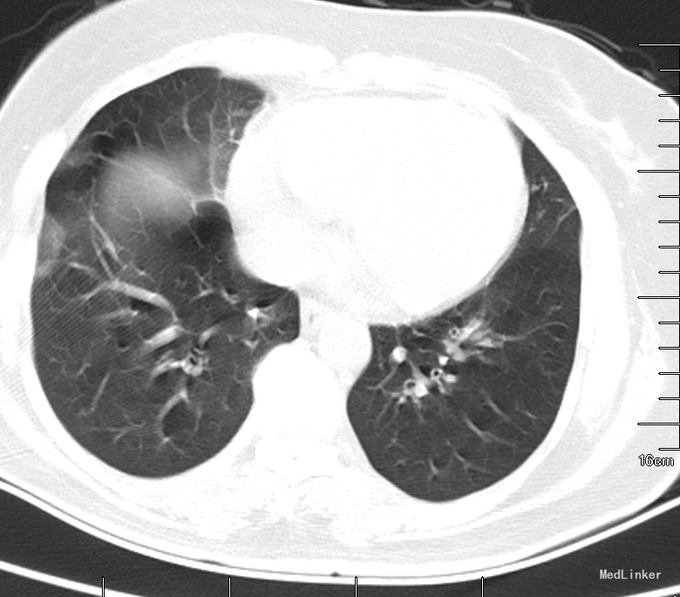

查体:体温:36.2℃,血压133/87mmHg,心率110次/分,呼吸:15次/分,查体合作,步入病房,周身皮肤未见皮疹及出血点,浅表未触及肿大淋巴结,颈软,结膜无苍白,巩膜无黄染,胸廓对称,双肺可闻及广泛干鸣音,心律齐,各瓣膜区未闻及病理性杂音,腹平软,无压痛、反跳痛及肌紧张,肝肾区无叩痛,移动性浊音阴性,双下肢无水肿。 血气分析:酸碱度 7.387;二氧化碳分压 40.5mmHg;氧分压 89.1mmHg; 血常规:白细胞计数 10.4*10^9/L;中性粒细胞百分比 64.1%;嗜碱细胞计数 0.07*10^9/L; CRP:C-反应蛋白 14.8mg/L;降钙素原检测(发光法):降钙素原 0.037ng/mL;总IgE测定:总IgE 192.0IU/mL; 肺炎支原体Igm抗体: 弱阳性(+-); 肺功能:混合性肺通气功能障碍,支气管舒张试验阳性,FEV1改善率25.4%。肺CT:双肺散在少许炎症。

诊断:支气管哮喘合并感染 予安赛玛平喘,开顺化痰,苏顺、普米克令舒、开顺联合雾化,顺尔宁口服平喘,改善通气,头孢噻肟钠舒巴坦钠抗感染治疗,信必可吸入平喘。